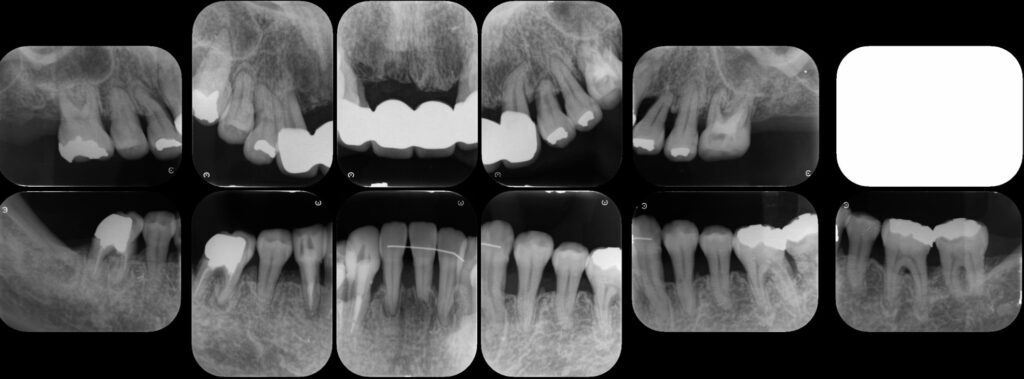

歯周再生療法 精密根管治療 歯周矯正治療 ジルコニアセラミック治療

Before

矯正治療

After

治療期間・回数

約3年・約20回

費用

1,400,000円(歯周矯正治療も含む)

治療のリスク

詰め物・被せ物の調整が難しく、割れた場合は再治療が必要。